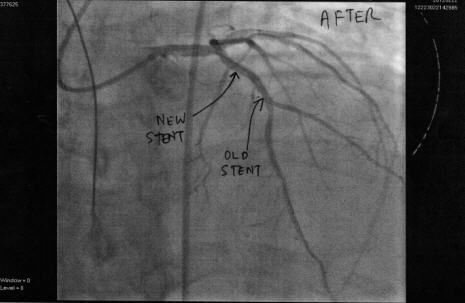

7 years ago I had a heart attack and a stent put in. Wednesday I had another heart attack due to that stent becoming completely blocked. I arrived home from hospital about 2 hours ago. I will try and get some scans made of the pictures tomorrow.